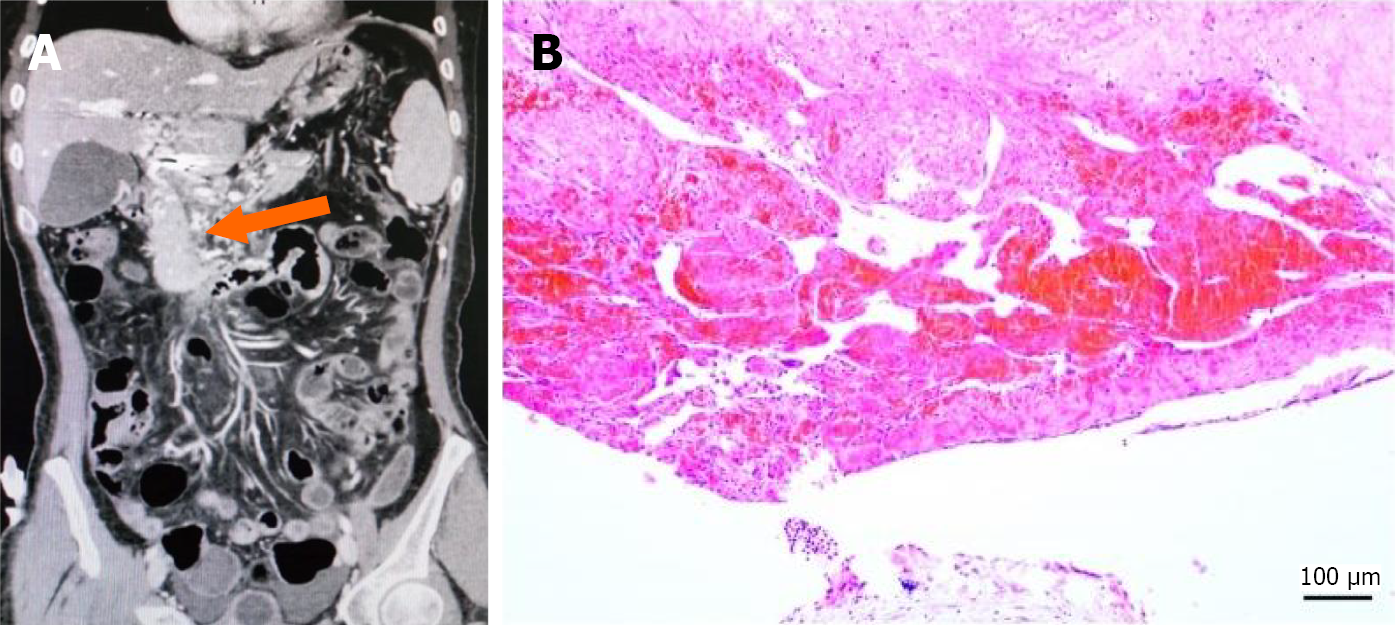

Cavernous transformation: In 22 patients (12.9%), the normal anatomical structure of the vessels at the site of the PVT was fully replaced by the formation of collateral vessels (Figure 4A).

Cavernous transformation was observed in 15 patients (13 underwent TIPS; 1 underwent surgical procedures; 1 underwent liver transplantation). The pathology was characterized primarily by fibrous tissue and vascular proliferation, with no intact vascular walls visible. Figure 4B demonstrates a HE stained section showing aggregates of red blood cells, fibrous tissue, and prominent proliferation of small vessels.